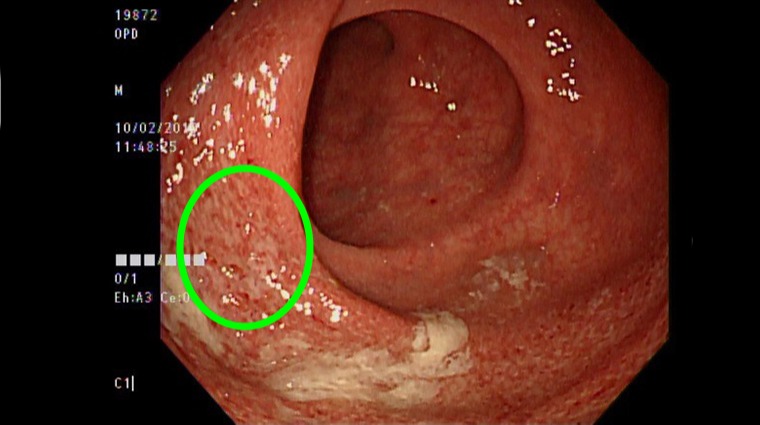

潰瘍性結腸炎是1種慢性、反覆性腸道發炎疾病,目前致病機轉不明,推測可能與遺傳、免疫系統失調、腸道共生菌失衡、飲食、壓力等因素有關。(圖/亞洲大學附屬醫院提供)

另1名徐女士每天平均腹瀉20次,感嘆「幾乎整天坐在馬桶上」,起初以為是腸躁症所致,但問診時她亦不覺得有生活壓力,經大腸鏡檢查發現左側直腸輕度發炎,病理報告確診為潰瘍性結腸炎;因潰瘍性結腸炎為罕見重大疾病,且無法治癒、未來癌變機率高,2位患者在確診當下均無法置信,甚至否定、崩潰、大哭,經詳細衛教並配合治療後,2人才破涕為笑,學習與疾病共處。

張家熙指出,潰瘍性結腸炎是1種慢性、反覆性腸道發炎疾病,目前致病機轉不明,推測可能與遺傳、免疫系統失調、腸道共生菌失衡、飲食、壓力等因素有關,好發於20歲左右年輕人,以及50至60歲中年人,通常會出現持續腹瀉、嚴重腹痛、解血便和黏液便,伴隨體重減輕、發燒等症狀,並可能造成腸道出血、腸道穿孔,增加罹患大腸癌機率等併發症。